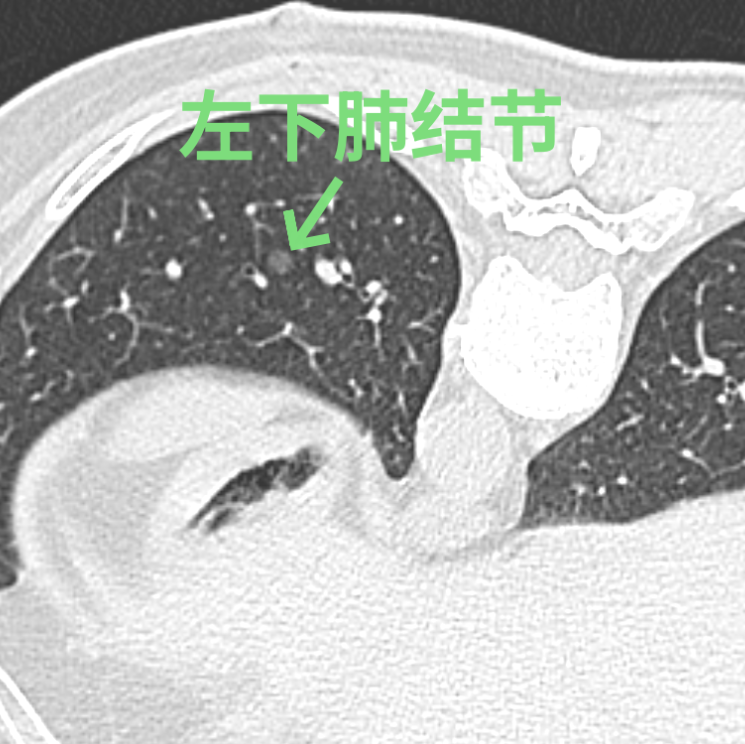

刘女士在体检时发现左肺有3个高危的磨玻璃结节,慕名找到我院胸部医学中心徐驯宇主任医师团队。在分析了刘女士的肺部影像资料后,徐驯宇发现刘女士左上肺的两个结节位置较浅表,其中一个结节最大径仅4.5mm,这类大小的结节在手术中不易定位;而左下肺的结节位置较深,如果全部采用手术切除的方法,将损失较多的正常肺组织,得不偿失。

经过徐驯宇主任医师、黄郴副主任医师和王捷阳医师的反复讨论,决定为刘女士实施杂交手术:首先由黄郴和王捷阳在CT引导下为刘女士左上肺的小结节打上金属钩作为标记,然后再对左下肺较深的结节进行热消融治疗;接着由徐驯宇主刀为刘女士进行胸腔镜下左上肺结节的切除。在术中,徐驯宇按照之前在CT引导下置入的金属钩,很快就定位到左上肺的磨玻璃结节,并进行精准的局部切除,整个过程仅耗时30分钟。术后的病理报告显示,这3个结节分别为两个原位癌和一个非典型腺瘤样增生。经过量身定制的杂交手术,刘女士顺利解除了肺部的3个健康隐患,3天就顺利恢复出院。

▲术中结节变化